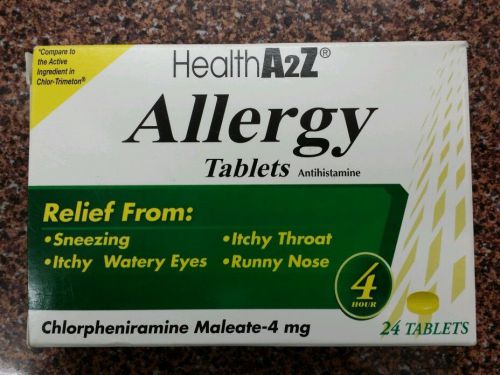

Health A2Z Allergy Tablet 24Ct EXP.07/2016